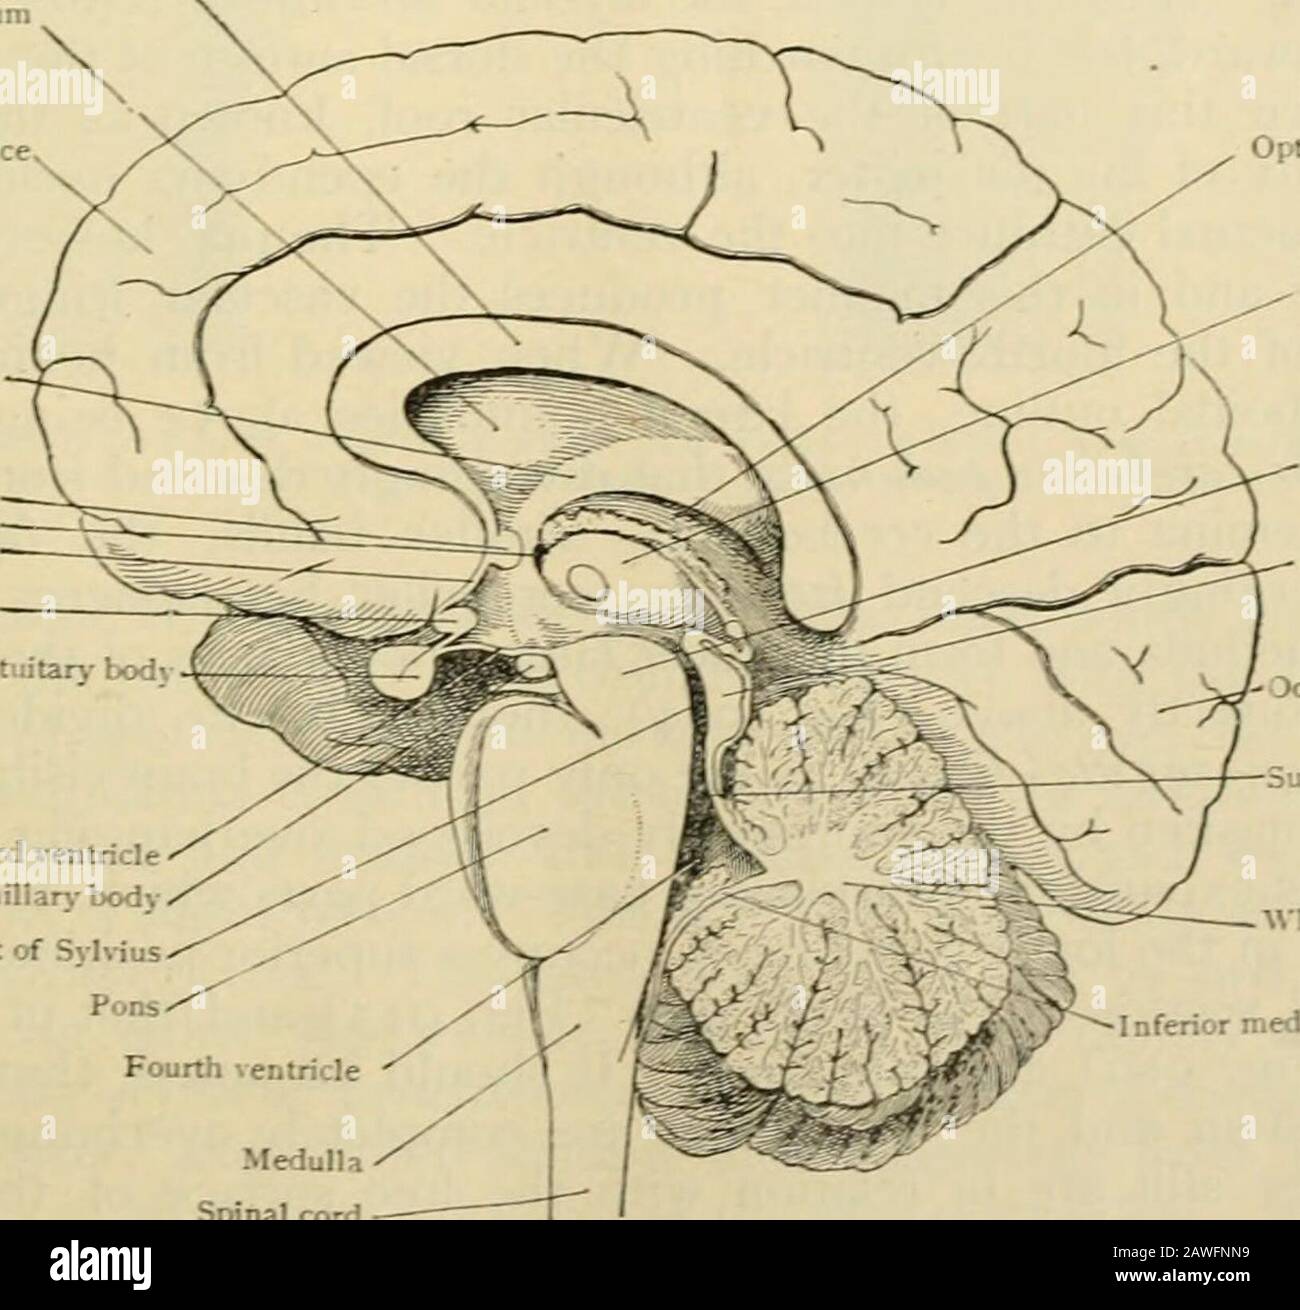

RM2AWFNN9–Menschliche Anatomie, einschließlich Struktur und Entwicklung und praktische Überlegungen d in einem sagittalen mesialen Abschnitt (Abb. 910) wird jede dieser Teilungen als mit einem Teil des Systems der Kommunikation von Räumen verwandt angesehen, die als die dritten Ventrikel des Lateralands, der Aquädukt von Sylvius und der vierte Ventrikel die oben genannten Gehirnhemisphären ausdehnen. Durch den Hirnstamm und unter dem Kleinhirn bis zum zentralen Kanal des Rückenmarks. Da die lateralen Ventrikel zwei innumerieren, ist die Theirstellung im Zusammenhang mit den Gehirnhemisphären, in denen sie liegen, lateral zum m

RMPFYB74–. Cunninghams Lehrbuch der Anatomie. Anatomie. PAETS abgeleitet aus dem ZWISCHENHIRN. 617 davon, welche das Aquädukt umgibt, ist direkt kontinuierlich mit der grauen Substanz der substantia perforata posterior und Tuber cinereum, und auf diese Weise kommt es zu der Oberfläche in der Unterseite des Gehirns. Die optic Chiasma kreuzen den Boden vor und markiert die Stelle, wo der Letzteren stetig mit der anterioren Wand des Hohlraums wird. Die vordere Wand des dritten Ventrikels wird durch die Lamina terruinalis, die sich nach oben erstreckt sich von der Optic chiasma gebildet. Die anteriore com-missure, wie es kreuzt von einem

RM2AN4TWY–Handbuch der allgemeinen, beschreibenden und pathologische Anatomie (Band 2). Ventrikel, ein. Ventrikel des Kleinhirns, b. Aquädukt von Sylvius, C. Dritten Ventrikel, d. Lateralen Ventrikel, 1. Vordere Horn, 2. Hintere Horn, 3. Absteigend Horn, II. Textur, III. Gewicht, IV. Konsistenz, Kap. Iii. Umhüllt des Gehirns. Abt. Ich. Pia - mater, I. des Rückenmarks, II. Von Hirn, ein. - Externe Pia mater, b. Interne pia-mater, ich. Choroid Plexus des vierten Ventrikel, ii. Choroid Plexus des Großhirns, Art.ii.Apert-syndrom Membran, Art. hi. Dura-mater, I. spinalen Dura-mater, II. Zerebrale Dura-mater